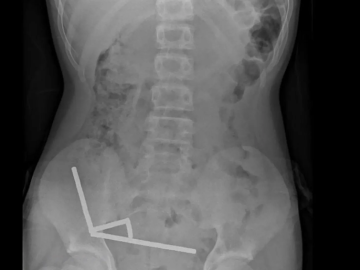

وبحسب تقرير نشرته صحيفة 'الغارديان' البريطانية، فقد نُقل الفتى، الذي لم يُكشف عن اسمه، إلى المستشفى بعد أربعة أيام من معاناته آلاماً شديدة في البطن، حيث أظهرت الفحوصات أن المغانط تجمعت في شكل أربع سلاسل مستقيمة داخل أمعائه.

وقال الأطباء في تقريرهم إن المراهق أقرّ بتناوله ما بين 80 و100 مغناطيس نيوديميوم عالي الطاقة، يبلغ حجم الواحد منها خمسة في اثنين مليمترات، مشيرين إلى أن هذه المغانط محظورة في نيوزيلندا منذ عام 2013 بسبب خطورتها البالغة على الأطفال.

وأوضحت الأشعة أنّ المغانط التصقت ببعضها في أجزاء مختلفة من الأمعاء، ما تسبب في نخر أنسجة بأربع مناطق من الأمعاء الدقيقة والأعور، واضطر الجراحون إلى استئصال الأنسجة المتضررة وإزالة المغانط. وتعافى الصبي بعد ثمانية أيام من العملية الجراحية.